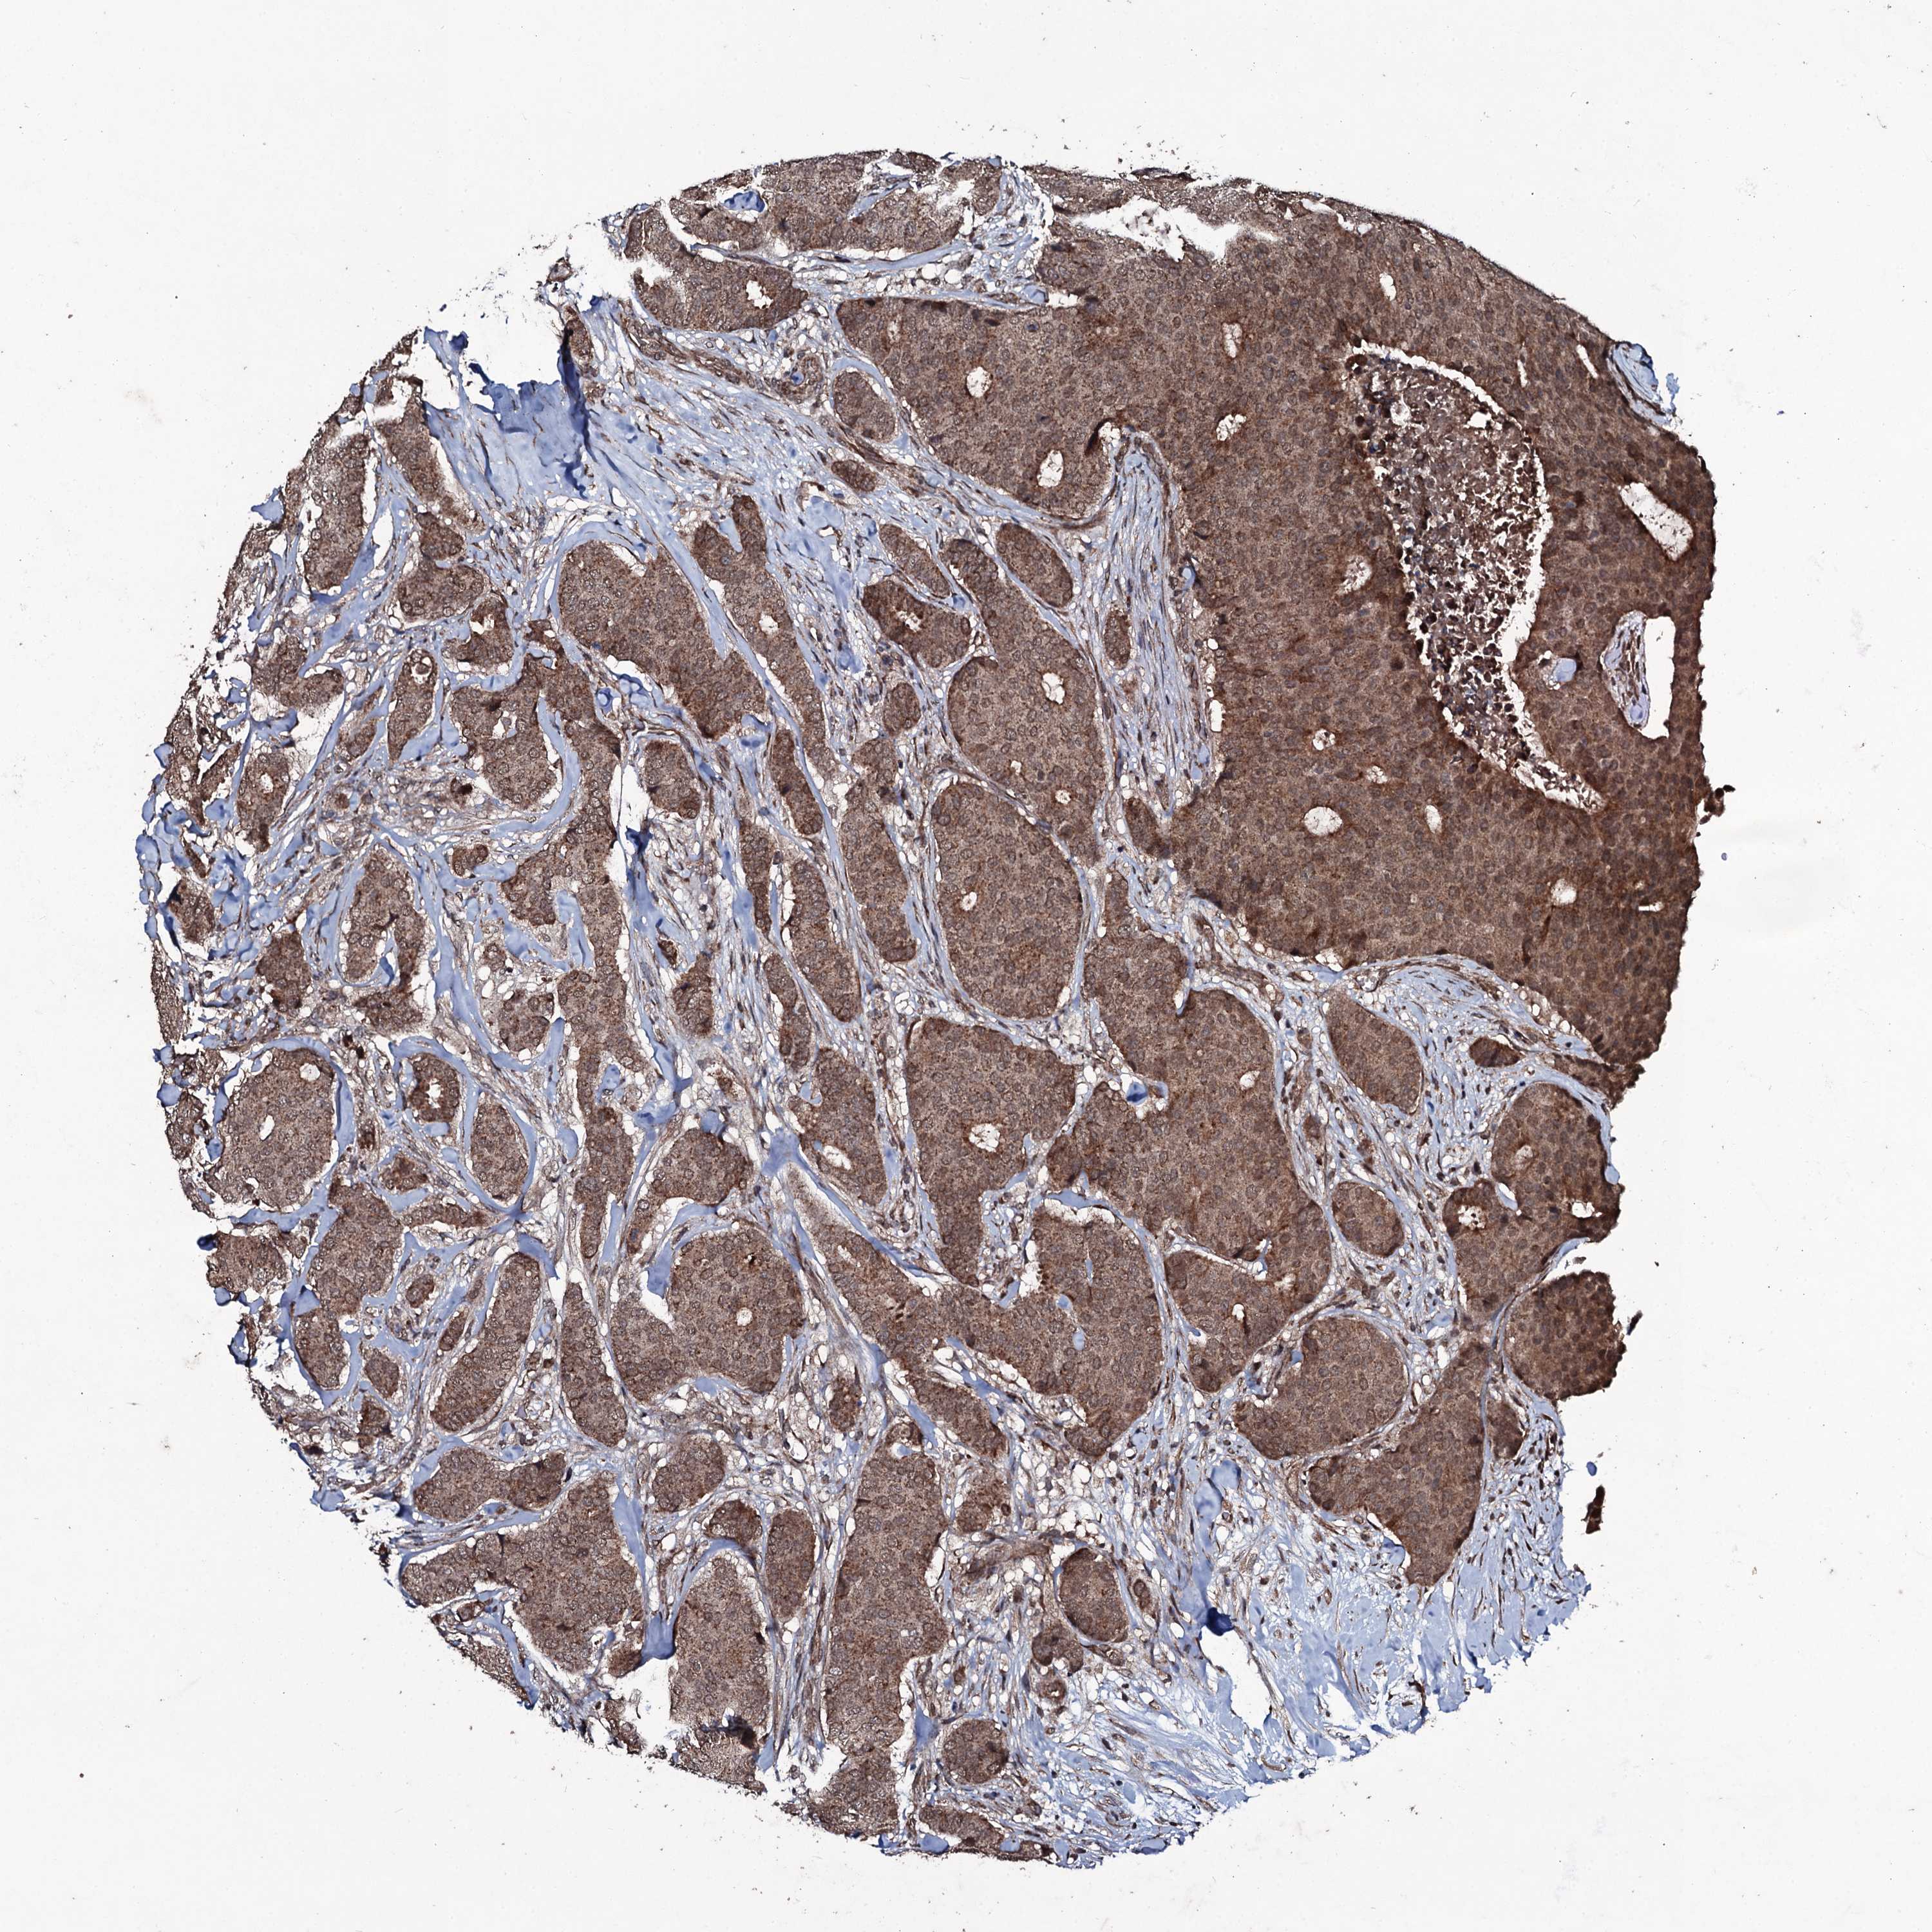

CANCER BREAST CANCER Show tissue menu

BRCA TCGA BRCA VALIDATION PROTEIN EXPRESSION